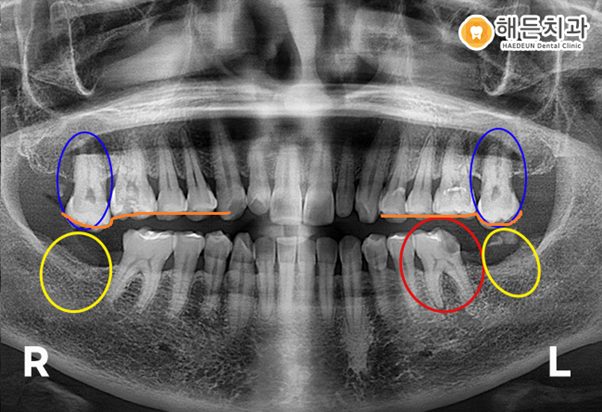

위 사진은 천안아산치과 해든치과에 내원하신 고*희 님의 치아 사진입니다.

위의 환자분은 빨간색 동그라미 표시를 한 왼쪽 아래의 어금니 일부가 파절 되었고, 씹을 때 통증이 있어서 내원해 주셨습니다.

더불어 양쪽 아래 최후방 어금니의 치아상실과 뿌리만 남은 곳에 임플란트 상담도 원하셨습니다.

구강 내 사진을 보시면 빨간색 동그라미 표시를 한 왼쪽 아래 어금니는 충치가 심한 상태이고,

노란색 동그라미 표시를 한 최후방의 치아는 일부만 잔존하는 것을 확인하실 수 있습니다.